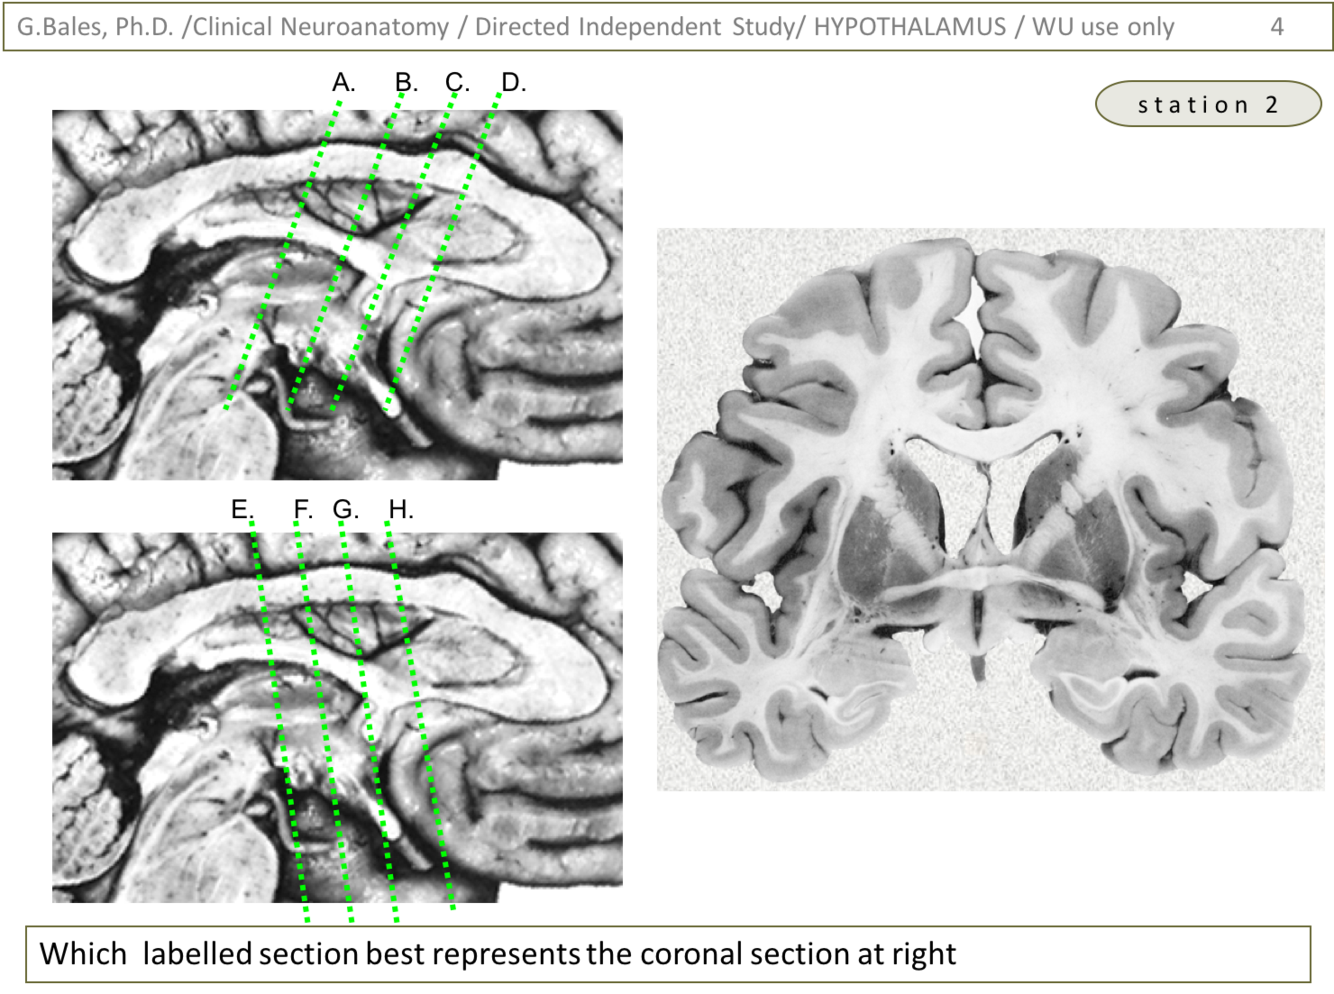

Most likely answer: C (lots of references from multiple labs; Coronal Brain Sections was major contributor).

Reasoning: we can first determine the picture is more anterior than posterior due to the shape of the lateral ventricles (head = butterfly, body = hawk). This helps with eliminating A and B as well as E and F. After that, you can look at the temporal lobe to notice that there is a slight bit of a ‘scroll’ like figure which could be the hippocampal complex just caudal to the amygdala. This would help eliminate H. All that is left is C, D, and G. Notice the small rounded bulges just lateral and inferior to the 3rd ventricle. This should be the optic tracts. This would indicate that the slice should be posterior to the optic chiasm. Hence, the only one that now fits is ‘C’.